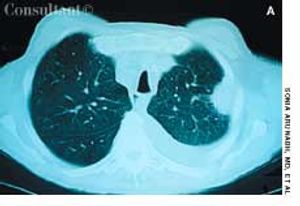

A 67-year-old man with a 5-month history of cough, shortness of breath, and pain in the left anterior chest wall sought medical evaluation. The patient denied fever, chills, and hemoptysis. He reported a recent weight loss of 25 lb. The patient had smoked cigarettes for 37 years.